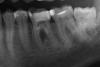

hopefull Опубликовано 3 февраля, 2011 Поделиться Опубликовано 3 февраля, 2011 Здравствуйте! Пишу почти в отчаянии, потому что сказали зуб удалять Зуб нижняя шестерка, самый большой. Для меня это трагедия, потому что зубы и так ужасные и с противоположной стороны уже удален жевательный. Пожалуйста, подскажите, можно ли и имеет ли смысл его спасти как-нибудь. Он меня не тревожит совершенно. Но на рентгене сильное затемнение между корней. Понимаю, что случай очень серьезный, несколько врачей разводили руками, мол, пройти можно лишь один канал, остальные не проходятся. Слышала про метод Депофореза, который чуть ли не чудеса творит. Но это очень дорого, насколько я понимаю. Очень хотела бы с кем-то посоветоваться, как быть и что делать в этом случае. Спасибо заранее за любые отклики! Ссылка на комментарий

juli63 Опубликовано 4 февраля, 2011 Поделиться Опубликовано 4 февраля, 2011 Здравствуйте! Пишу почти в отчаянии, потому что сказали зуб удалять Зуб нижняя шестерка, самый большой. Для меня это трагедия, потому что зубы и так ужасные и с противоположной стороны уже удален жевательный. Пожалуйста, подскажите, можно ли и имеет ли смысл его спасти как-нибудь. Он меня не тревожит совершенно. Но на рентгене сильное затемнение между корней. Понимаю, что случай очень серьезный, несколько врачей разводили руками, мол, пройти можно лишь один канал, остальные не проходятся. Слышала про метод Депофореза, который чуть ли не чудеса творит. Но это очень дорого, насколько я понимаю. Очень хотела бы с кем-то посоветоваться, как быть и что делать в этом случае. Спасибо заранее за любые отклики! зуб случайно не розового цвета? похоже уже пытались в каналах поработать, на ступеньку похоже. депофорез-это дохлый номер. есть стоматологи эндодонтисты(специалисты по лечению и распломбировке коневых каналов). вам нужен один из них. только по снимку сложно сказать о том, можно ли пройти каналы в данном зубе или нет, но шансы есть. Ссылка на комментарий

Bier Опубликовано 4 февраля, 2011 Поделиться Опубликовано 4 февраля, 2011 да там небось перфорация, на мой взгляд - этот зуб удалять. Ссылка на комментарий

hopefull Опубликовано 7 февраля, 2011 Автор Поделиться Опубликовано 7 февраля, 2011 А каналы пройти пытались или по снимку окрестили их непроходимыми? Не уповайте на депофорез- результаты спорные. А можно еще вопрос? Если каналы пройдут, допустим с микроскопом, ведь разрежение не под ними, а между корнями. Т.е. источник бактерий не ясен (может и правда перфорация дна зуба), а депофорез, насколько я поняла, тем и хорош, что дезифицирует все внутри, убивая бактерии. Т.е. этот диоксид меди-кальция имеет шанс проникнуть через полости в зубной ткани в простанство между корней. Именно поэтому мне казалось, что он может помочь. А если даже пролечить каналы, то до воспаления между корнями никак не добраться Разве не так? А можно еще вопрос? Если каналы пройдут, допустим с микроскопом, ведь разрежение не под ними, а между корнями. Т.е. источник бактерий не ясен (может и правда перфорация дна зуба), а депофорез, насколько я поняла, тем и хорош, что дезифицирует все внутри, убивая бактерии. Т.е. этот диоксид меди-кальция имеет шанс проникнуть через полости в зубной ткани в простанство между корней. Именно поэтому мне казалось, что он может помочь. А если даже пролечить каналы, то до воспаления между корнями никак не добраться Разве не так? И еще у меня довольно глупый, наверное, вопрос: что будет, если оставить все так, не удалять? Если он никак не беспокоит, и все равно его теряю, зачем удалять так быстро? Лучше оттянуть это максимально, по-моему. Подозреваю, что речь пойдет о вреде воспалительного процесса в организме? По сравнению с потерей зуба, это почти ерунда для меня. Вот что будет с ним самим впоследствии, интересно! Он сам вывалится от полного отмирания кости под ним? Извините за вопрос чайника Ссылка на комментарий